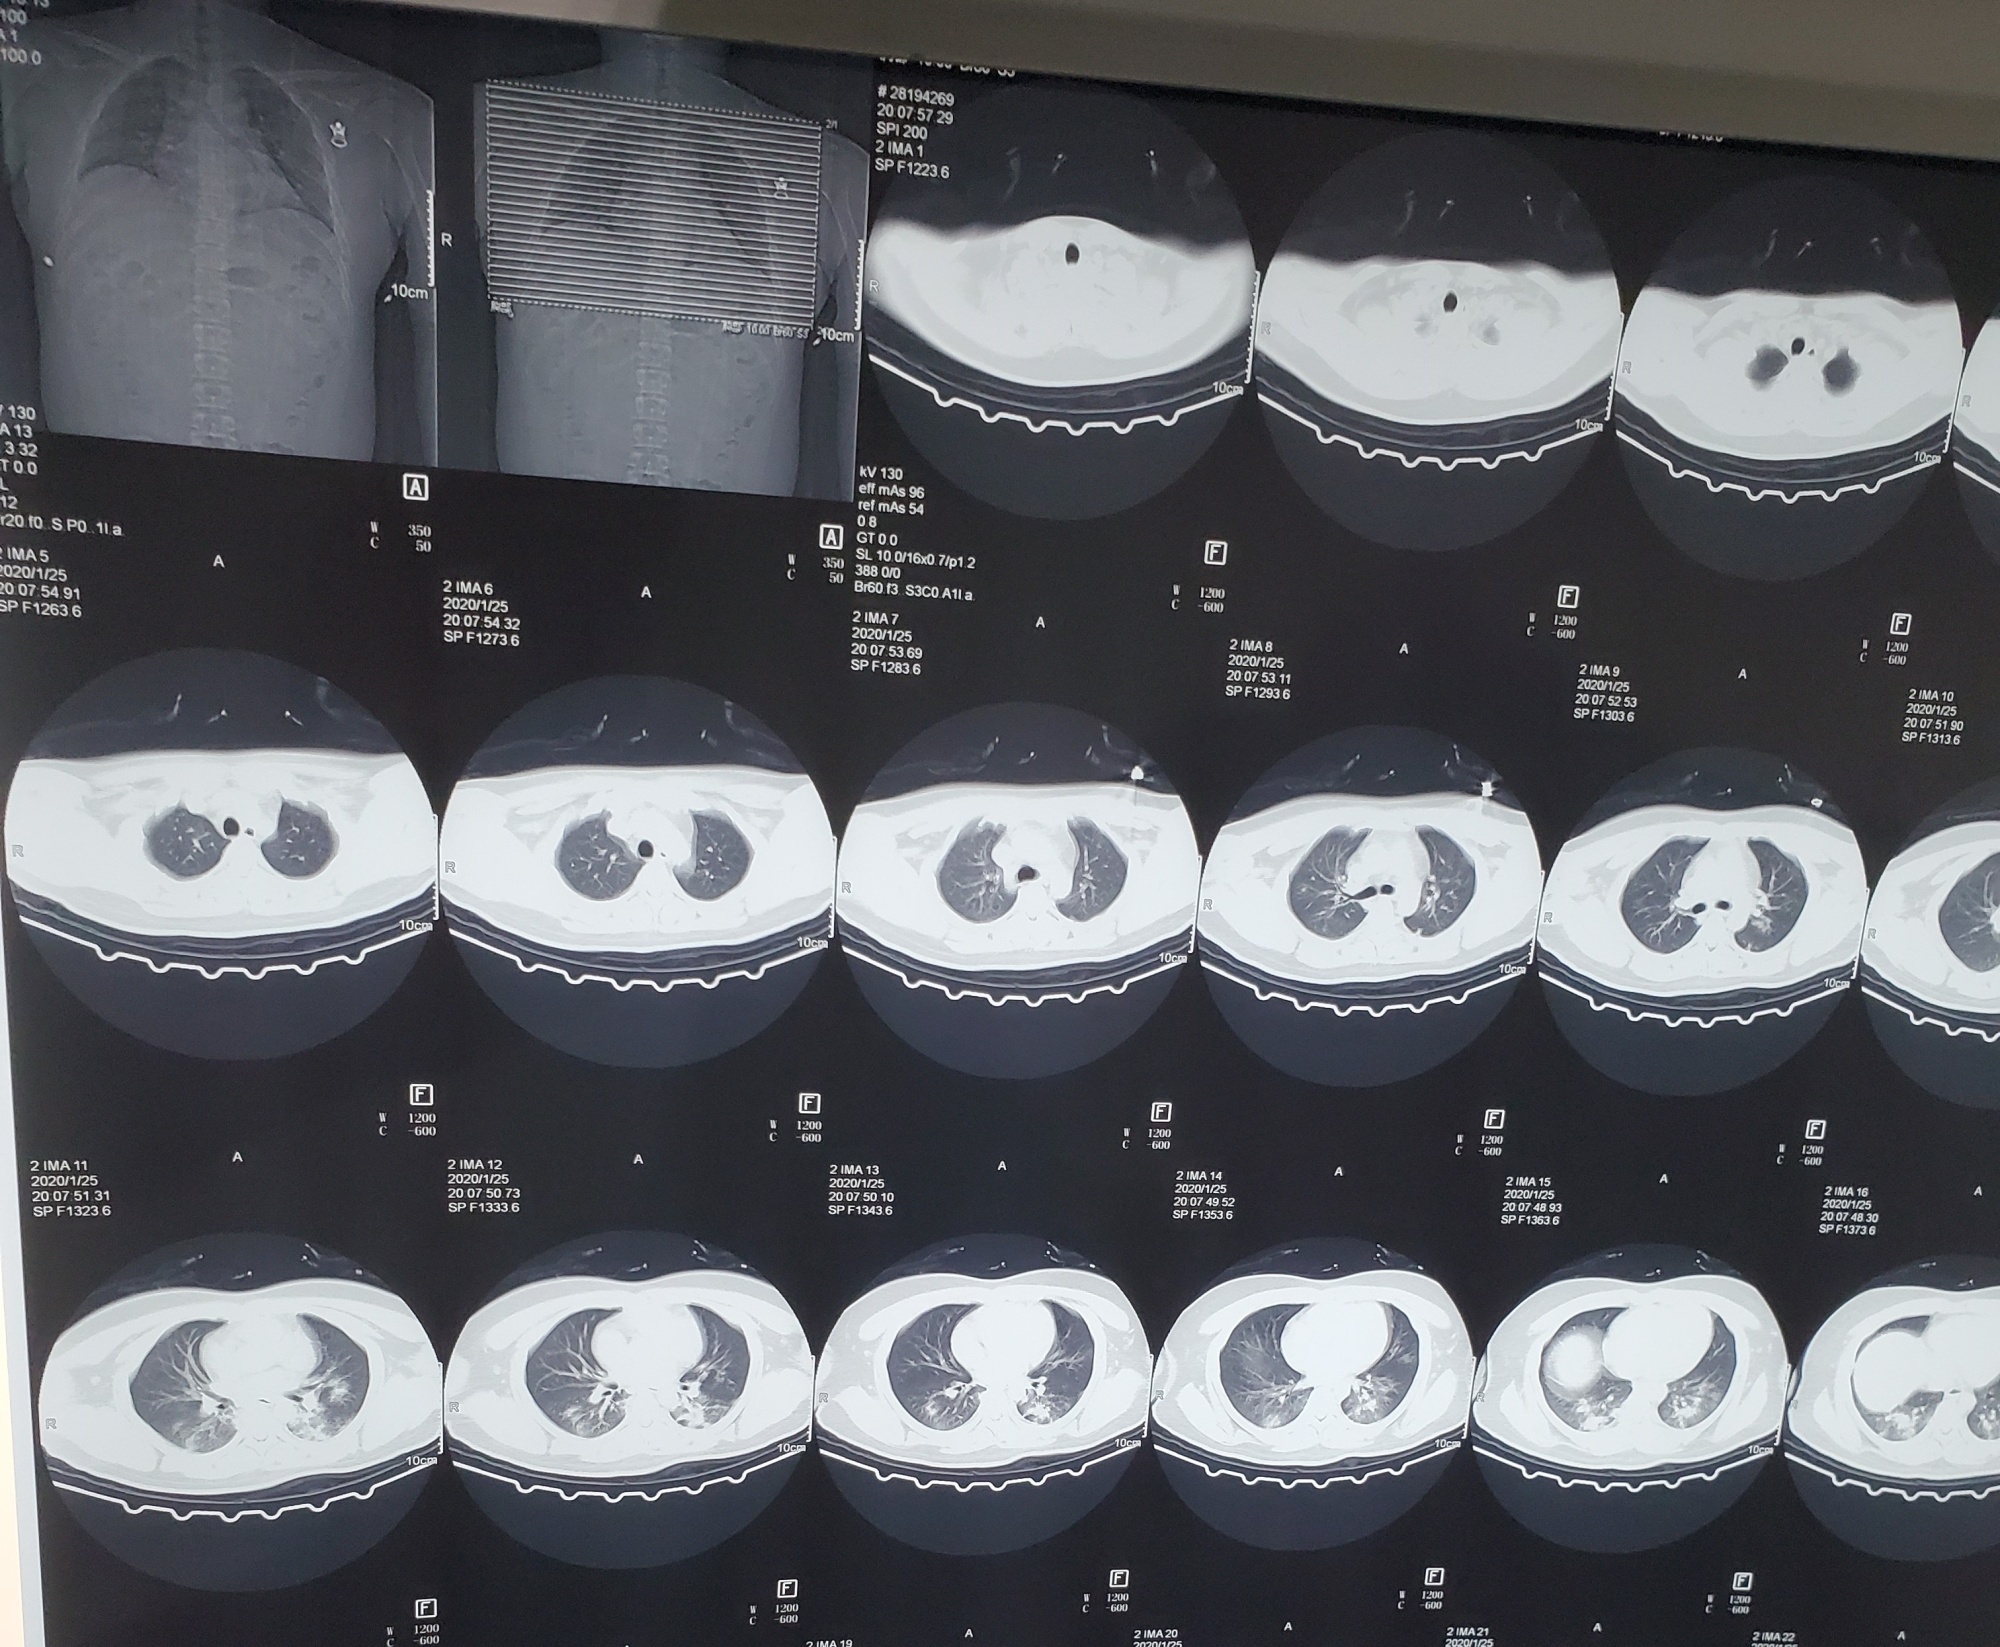

virus corona lay lan anh 2

Hình chụp CT phổi của Tiger Ye. Ảnh: Bloomberg.

Tình trạng của Tiger nặng hơn tại thời điểm này. “Tôi ho như sắp chết”, anh nhớ lại. Đến viện kiểm tra, hình chụp CT của nam bệnh nhân cho thấy bệnh của anh có chuyển biến xấu. Các bác sĩ đánh giá rất có khả năng Tiger đã bị lây nhiễm virus corona và virus này đang lây lan, tấn công phổi.